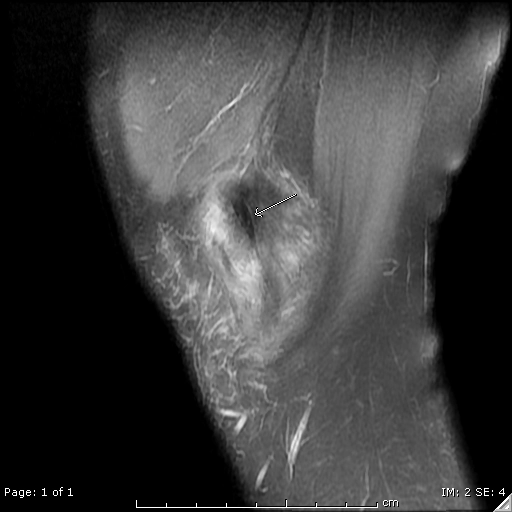

Thoái hóa nhầy của dây chằng chéo trước (Anterior cruciate ligament (ACL) mucoid degeneration)